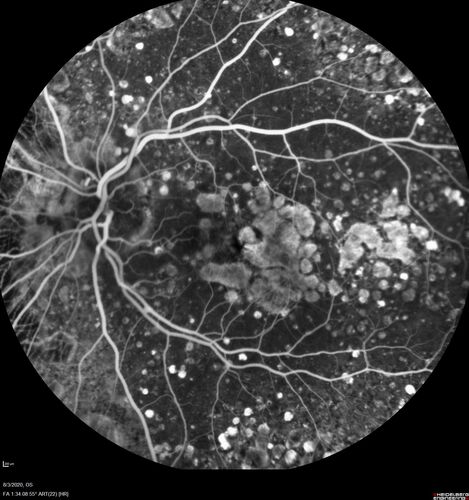

Dry AMD geographic atrophy and cystoid macular edema

79 year old vision is in for a checkup with no visual complaints in the left eye.  This is her better eye.  VA 20/200 OD, 20/50 OS.  3 years ago she had a CRVO in the left eye.  She is also diabetic for 20 years, has carotid insufficiency and anemia.  Left eye shows CME.  This was not treated and the vision improved to 20/40 over the next year although mild edema persisted.